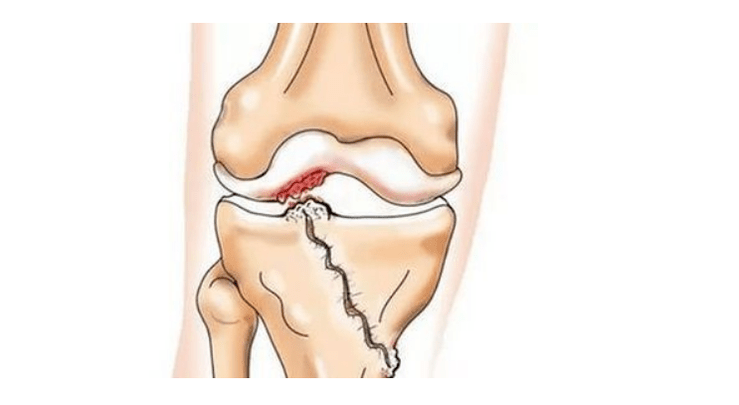

- injuries (fractures, ruptures of the meniscal and anterior cruciate ligaments).Unfortunately, in any person, regardless of age, these injuries lead to excessive stress on the cartilage.A fracture of any part of the bones covered with cartilage is accompanied by the formation of an irregularity - a "step".In this area, during displacement, abrasion occurs and arthrosis is formed;

With arthrosis (osteoarthrosis), in addition to the progressive destruction of cartilage, the loss of its elasticity and shock-absorbing properties, bones are gradually involved in the process.Under load, sharp edges (exostoses) appear, which are mistakenly considered "salt deposits" - in classic arthrosis no salt deposits occur.As osteoarthritis progresses, it continues to “eat” the cartilage.Then the bone is deformed, cysts form there, all structures of the joint are affected and the leg bends.

In the second phase, the cartilaginous layer becomes significantly thinner and in some places is completely absent.Osteophytes appear along the edges of the joint surfaces.The qualitative and quantitative characteristics of the synovial fluid of the joint change: it becomes denser, more viscous, which leads to a deterioration of its nutritional and lubricating properties.The pain is more prolonged and intense and a crunching sound is often heard during movement.There is mild to moderate limitation of movement and slight deformation of the joint.Taking analgesics helps relieve pain.

Lack of cartilage in most affected areas, severe sclerosis (hardening) of the bone, many osteophytes, and a strong narrowing or absence of the joint space.The pain is almost constant, the gait is impaired.Mobility is severely limited and joint deformation is evident.NSAIDs, physiotherapy and other standard methods for treating knee osteoarthritis are ineffective.